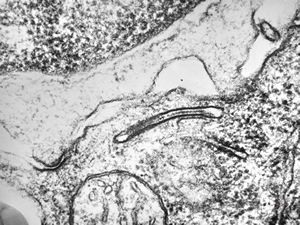

F, 39y. | collagenous and elastin fibers from corium

F, 39y. | collagenous and elastin fibers from corium